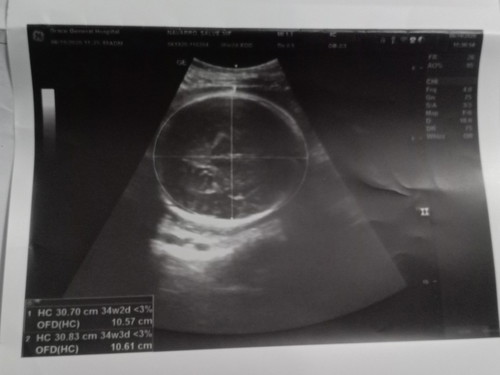

Kung first UTZ ang susundin 37 weeks & 1 day ako ngayon. Hindi ko kasi matandaan LMP ko. 😅 EDD ko sa first UTZ July 13, 2020. EDD ko sa BPS July 25, 2020. #TeamJuly